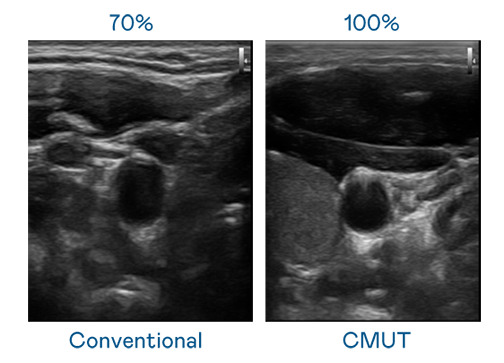

CMUT 技術是一種用電容式微機電元件來產生超音波訊號的技術。與傳統 PZT 壓電式技術相比,CMUT 頻寬增加 30%,更寬頻的超音波訊號讓影像解析度大幅提升,是實現高影像品質醫療超音波掃描、促進精準醫療發展的關鍵技術。

大頻寬帶來超清晰影像

超音波影像的解析度高低,首先取決於探頭能發出的訊號頻寬。z6mg人生就是博 CMUT 可提供高清晰的超音波訊號,提供高頻寬、高靈敏度、影像紋理細節更高的超音波影像,協助醫護人員縮短影像判讀時間及利用精準的醫療影像進行診斷。